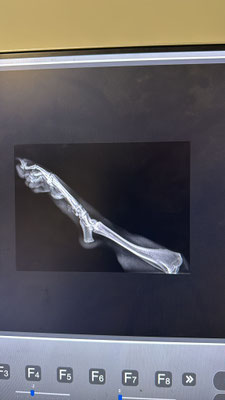

Sie hat Verletzungen an den Hinterbeinen